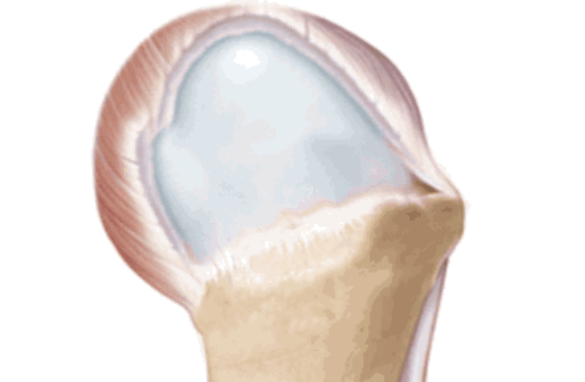

按照损伤程度分为部分撕裂( MR准确性>85% )和完全撕裂(MR准确性>95% )。

部分撕裂按照受损部位又分为滑囊面、关节面及肌腱内撕裂,在MRI上可以清晰的看到其受损部位。按照损伤深度分为1级:撕裂深度小于3mm,2级:撕裂深度在3-6mm,3级:撕裂深度大于6mm。

全层撕裂按照范围分为小撕裂:撕裂口<1cm,中撕裂:撕裂口1-3cm,大撕裂:撕裂口3-5cm,巨大撕裂:撕裂口>5cm。高清晰度的MRI是可以测定撕裂范围的。

按照撕裂的形状又分为新月形撕裂、U形撕裂、L形撕裂、倒L形撕裂、巨大回缩性/不可移动性撕裂。想要判断损伤的形状需要在MRI上利用多个平面、多张照片来分析。